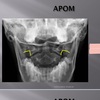

APOM ANATOMICAL LANDMARKS

maxillary sinus

29

frontal sinus

30

nasal aperature

31

nasal spine + septum

32

lower teeth

33

upper teeth

34

mandible

35

jugular process

36

A-P open mouth

rim of foramen magnum

37

anterior arch c1

38

posterior arch c1

39

A to P open mouth

lateral mass of c1

40

transverse process c1

41

medial inferior tip of occipital condyles

42

mastoid air cells

43

A-P open mouth view

pedicle shadow c2

44

spinous process c2

eop-iop

atlantal-axial joint space

vertebral bodies c2-c7

inferior articular surface c1

superior articular surface c1

A-P cervical

uncinate process of cervical vertebra

occipital-atlantal joint space

odontoid process